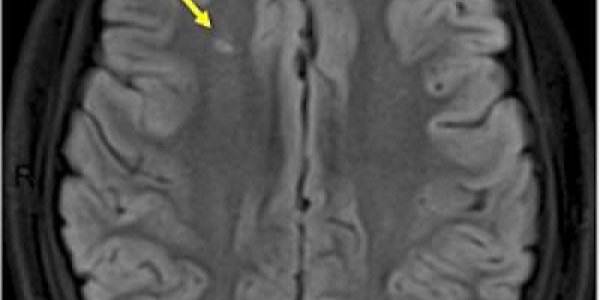

A long-term, large-scale population-based study of individuals aged 55 years or older in the general population researchers has found a four-fold increased risk of developing dementia or Alzheimer's…